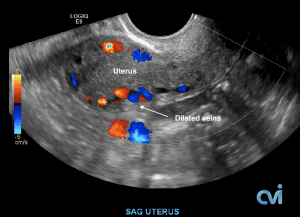

PCS can be diagnosed by Ultrasound or CT of the Abdomen and Pelvis.

Ultrasound examination is the least invasive study and can identify enlarged veins around the uterus and pelvis. However, sometimes the veins in the pelvis are difficult to see or can be missed if the technician is not specifically looking in the right area.